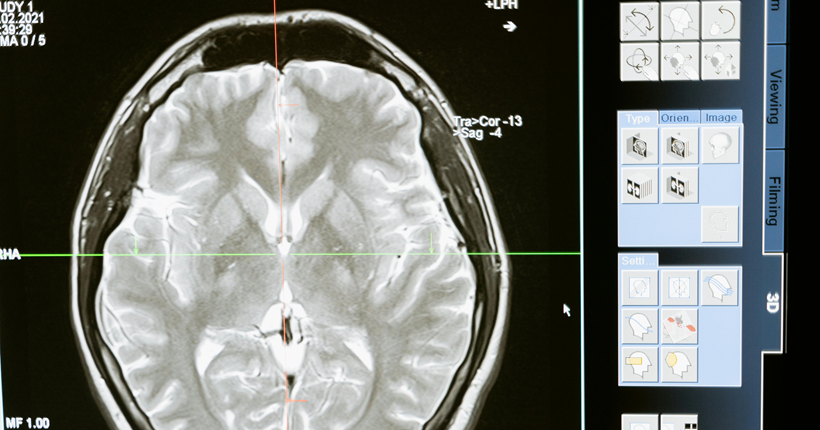

Imagen de un escáner cerebral.

Los principales factores de riesgo encontrados son edad avanzada, menor educación, poca actividad física, hábito de fumar, consumo excesivo de alcohol, hipertensión arterial, diabetes, obesidad, depresión, pérdida o disminución de la audición, aislamiento social, los traumas craneales y la contaminación ambiental. Los biomarcadores fundamentales son: los marcadores que se utilizan en los estudios de neuroimágenes como la tomografía por emisión de positrones (PET) Amiloide, PET tau, PET con fluorodesoxiglucosa (FDG); y en líquido cefaloraquídeo y plasma: Aβ42, Aβ42/Aβ40, p tau 217, p tau 181, proteína gliofibrilar ácida (GFAP), y neurofilamentos de cadena ligeras. Se reconoció el uso de los parámetros cuantificados en el P300 como biomarcadores complementarios clasificadores de la presencia y del nivel de disfunción cognitiva de etiología enfermedad de Alzheimer posible.